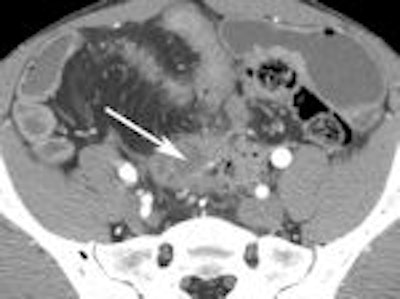

A 2007 study by University of Michigan gastroenterologist Dr. Peter D.R. Higgins showcases the diagnostic power of CT enterography (CTE) for evaluating small bowel Crohn's disease.

Higgins concluded that CTE offered complementary information about symptoms of obstruction in Crohn's disease (Inflammatory Bowel Diseases, March 2007; Vol. 14:3, pp. 262-268).

The following images from Higgins' study illustrate some of the clinically relevant findings about Crohn's disease that can be made with CTE.

Left: Fatty proliferation. Right: Lymph node enlargement.